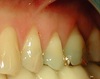

Cas 4

Une greffe gingivale est souvent réalisée dans le même temps opératoire que la pose de l'implant dans les secteurs esthétiques afin de regonfler les tissus mous et redonner une symétrie au sourire